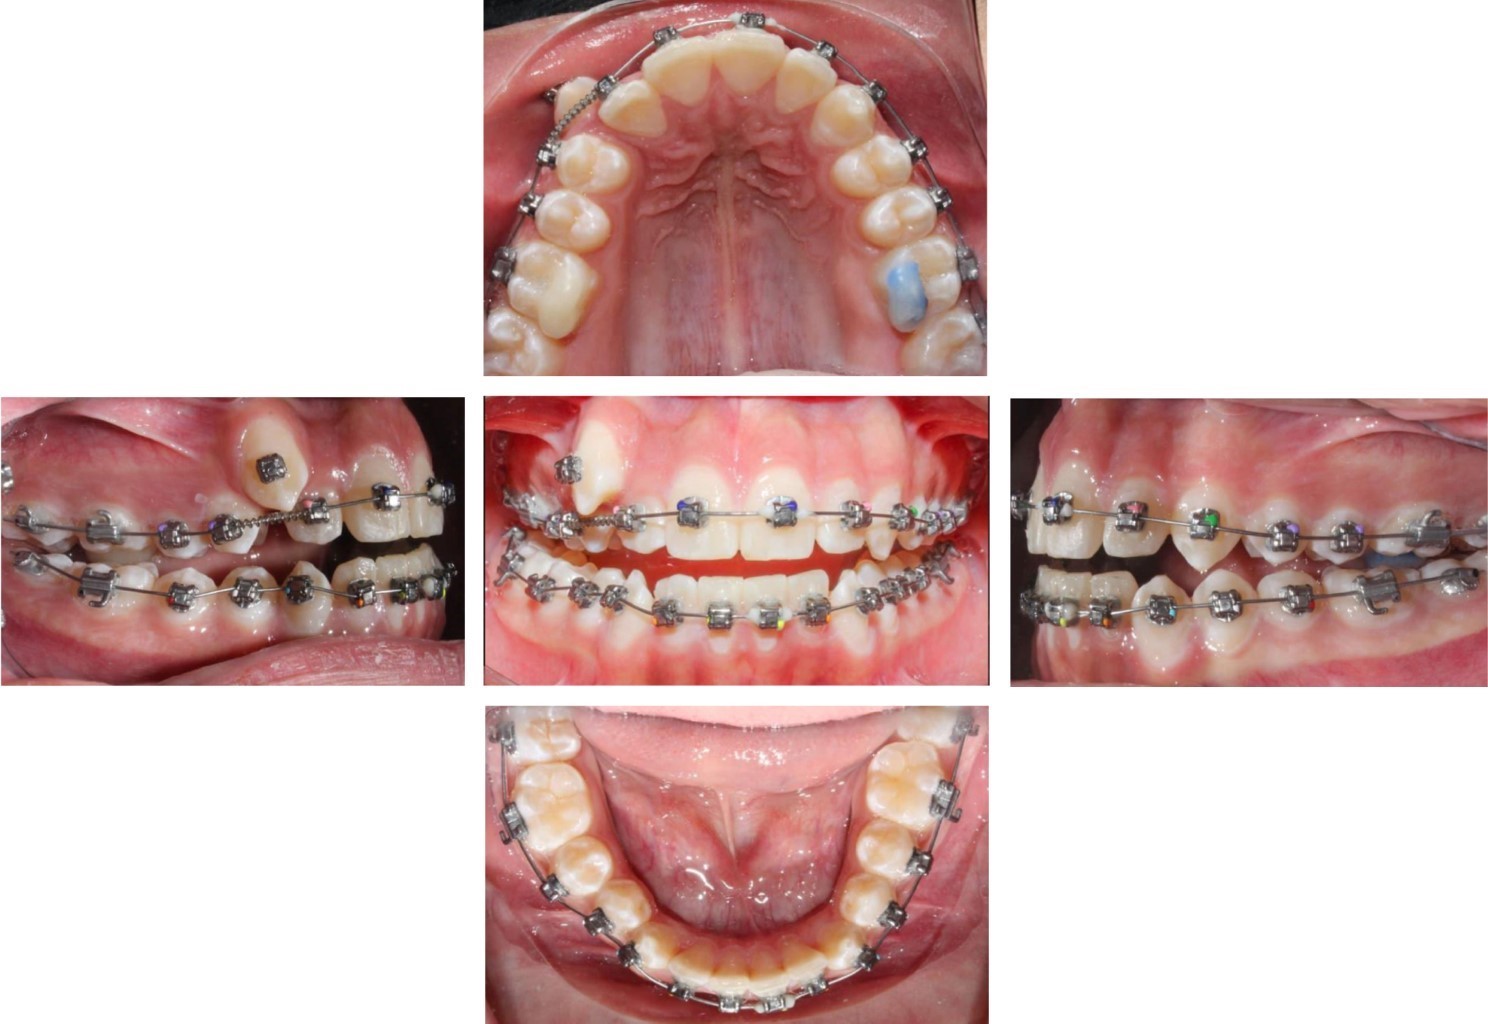

Posteriormente se incorporó el canino al arco y se colocó un arco 0.014" CuNiTi. Una vez incorporado a la arcada, se pasó a un arco 0.018" CuNiTi y se continuó con el uso de elásticos vector clase II ligeros de ¼ 2.5 oz. Tres meses después se colocó un arco 0.014" × 0.025" CuNiTi superior y 0.018" CuNiTi inferior (tres meses). A continuación, se cambió a un arco 0.018" × 0.025" CuNiTi superior e inferior y se colocó un botón en el primer molar superior derecho para el uso de elástico cruzado al primer molar inferior derecho de 3/16 4.5 oz (Figura 5). Después de tres meses se retiraron los bite turbos y se colocaron arcos 0.018" × 0.025" de acero superior e inferior (Figura 6). Por último, se retiró la aparatología y se colocó un retenedor fijo inferior y retenedor tipo essix superior.

Se consiguieron los objetivos de tratamiento planteados: se descruzó la mordida posterior de lado derecho; se estableció clase I canina, clase I molar, y la forma de arco ovoide tanto superior como inferior y se logró mantener el perfil facial del paciente (Figura 7). Mediante la radiografía se apreció un buen paralelismo radicular (Figura 8A) y con la lateral de cráneo final, a la que se le realizó la superposición, se observó que se consiguió establecer una mejor relación anteroposterior (Tabla 1, Figura 8B y C).